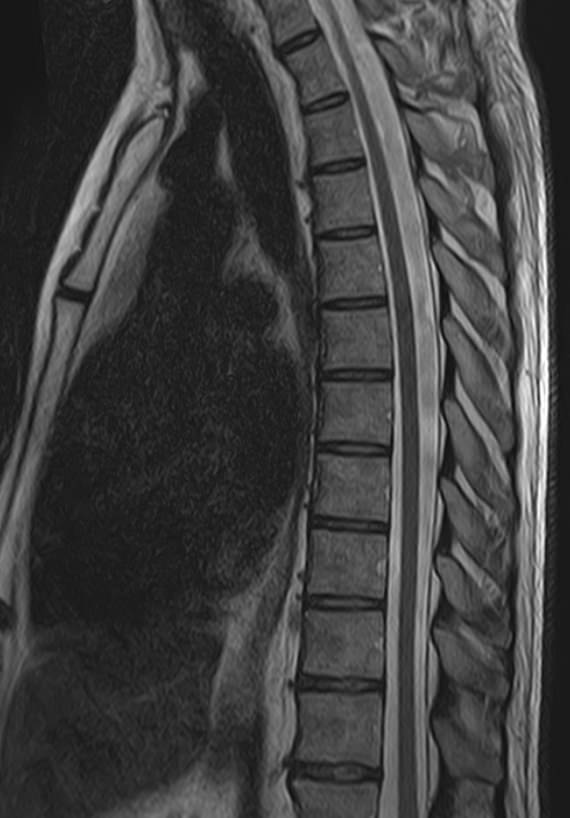

Магнитно-резонансная томография является наиболее чувствительным и эффективным методом диагностики различных заболеваний позвоночника. Метод позволяет оценить состояние костных структур позвонков, позвоночного канала с расположенным в нем спинным мозгом и окружающих мягких тканей, кроме того является основным способом диагностики демиелинизирующих заболеваний спинного мозга.

В клинике «Доступная медицина» установлен новейший высокопольный томограф экспертного класса TOSHIBA VANTAGE TITAN 1,5 Тесла, на котором выполняется комплексное обследование позвоночника. За счет высокой напряженности магнитного поля аппарат при сканировании создает изображения на плоскости превосходной четкости, затем с помощью компьютерных приложений данные преобразуются в изображения трехмерного формата, что обеспечивает точность и достоверность диагностики.

• Дегенеративные-дистрофические заболевания в шейном, грудном, пояснично-крестцовом отделах позвоночника и копчике (спондилез, спондилоартроз, остеохондроз).

• Грыжи межпозвонковых дисков (протрузии, экструзии).

• Стеноз (сужение) позвоночного канала.